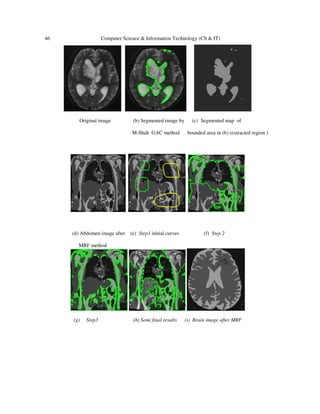

Original image (b) Segmented image by (c) Segmented map of

(d) Abdomen image after (e) Step1 initial curves (f) Step 2

MRF method

So we superimposed the edge of the different regions in the image using Mumford-Shah method

after we chose few closed curves represent different intensity area in our image. For example as

shown in Figure.5 (e&j). So our results accuracy depend on, if the results of MRF is accurate

then the regions boundaries are in correct position as shown from the figures above. Also in this

method; if we want to choose any region in the image and to define its edge, we can do all that.

Then we can calculate some region information such as the area of that region , region map and

contour length clearly. We can use different kind of images to extract different features (roads ,

rivers , agricultural areas …etc ) as in remote sensing images.